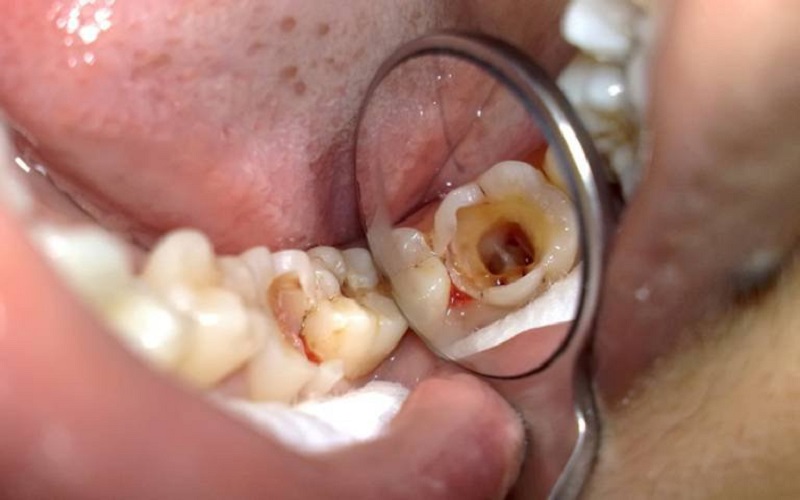

Mở lối vào buồng tủy răng, làm sạch và tạo hình ống tủy

Bác sĩ sử dụng mũi khoan để mở đường vào buồng tuỷ răng. Đường vào này rất quan trọng. Phải đủ rộng để có thể lấy sạch tuỷ răng trong toàn bộ hệ thống ống tuỷ và dễ dàng trám kín ống tuỷ sau này.

Bác sĩ sử dụng dụng cụ gọi là “trâm” để lấy sạch tuỷ răng, vi khuẩn…. Tạo hình ống tuỷ đồng thời kết hợp với việc bơm rửa nhiều lần cho hiệu quả việc làm sạch được nâng cao. Việc tạo hình ống tuỷ giúp cho việc làm sạch và trám bít ống tuỷ sau này được thuận lợi.

Để đảm bảo cho toàn bộ hệ thống ống tuỷ được làm sạch. Cần phải chụp các phim đo chiều dài chân răng hay sử dụng máy định vị chóp. Theo đó bác sĩ sẽ phải làm sạch, tạo hình tới đúng chiều dài chân răng. Đảm bảo không còn mô tuỷ hay vi khuẩn còn sót lại trong ống tuỷ.